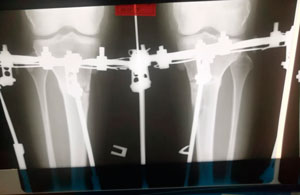

на фиксации

IMG_3925-30-06-19-08-20.JPG

IMG_3932-30-06-19-08-20.JPG